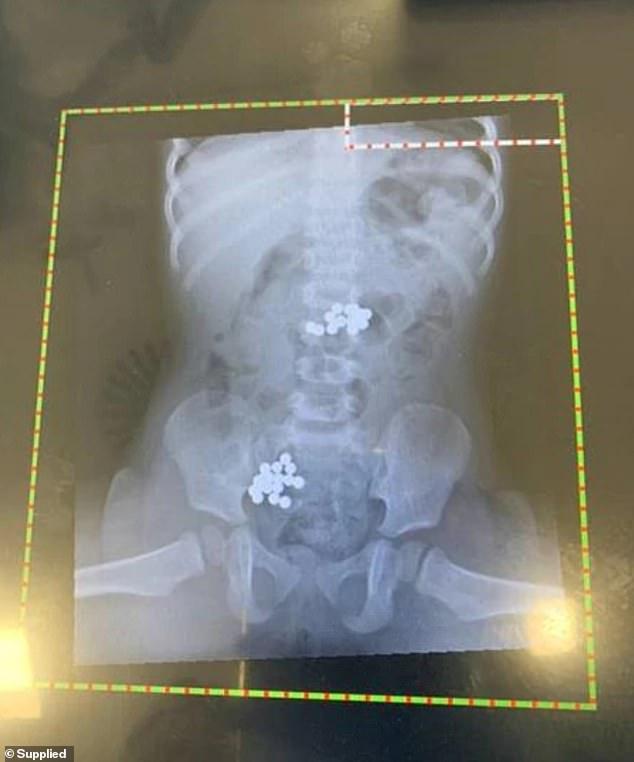

据《每日邮报》5月5日报道 , 澳大利亚墨尔本一名十八个月大的女童出现剧烈腹痛 , 母亲见状赶忙将她送往医院 , 在为女孩拍摄X光片进行检查后 , 医生竟在她的肚子里发现了几十块磁铁滚珠 。

据悉 , 这名吞下磁铁的女孩名叫伊莫金·弗格森(Imogen Ferguson) , 十八个月大的她在母亲不注意的时候 , 竟吞咽了32颗磁铁滚珠 , 送医后医生赶忙为她做了紧急手术 。

将女儿送医后 , 布朗说:“医生给她做了X光检查 , 发现她的胃部和肠子里有32个磁铁滚珠 。 ”此外 , 经检查医生还发现小女孩的姐姐也吞下了两个磁铁滚珠 。